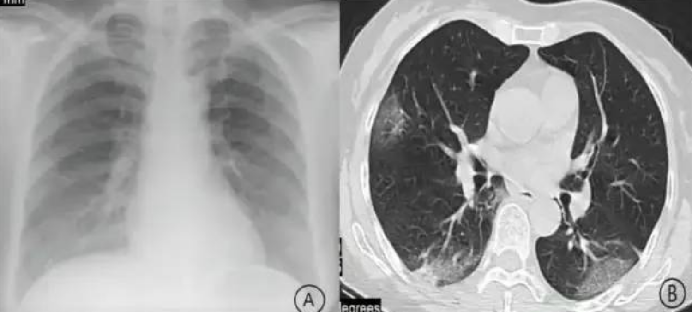

所谓的“白肺”,并不是肺变成了白色,而是在CT影像上,正常的黑色肺组织被大范围的白色渗出阴影所覆盖。这代表着肺泡被炎症液体和细胞填充,失去了气体交换功能。一项针对2020年初住院患者的临床研究显示,在16例患者中,有1例危重患者就出现了典型的双肺“白肺”改变。这是病情危重、需要呼吸机支持的明确标志。